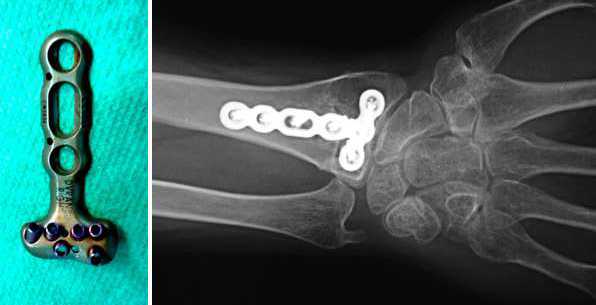

Plaque anatomique posée suite à une fracture du poignet

Fixation par plaque anatomique

En cas de fracture déplacée ou instable du radius, une fixation de l’os peut être réalisée par mise en place d’une plaque anatomique spécialement adaptée à l’anatomie de cet os, par sa forme et par sa faible épaisseur. Les vis peuvent se verrouiller dans l’os et également dans la plaque.

L’incision est réalisée sur la face antérieure du poignet, permettant ainsi d’accéder au radius.